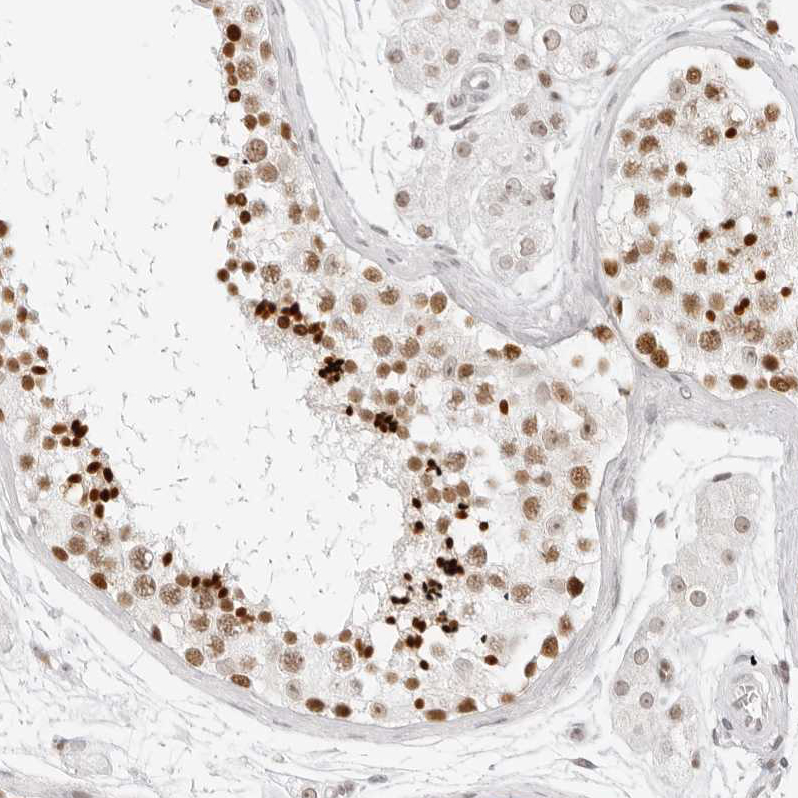

Immunohistochemistry analysis in human testis and cerebral cortex tissues using HPA027573 antibody. Corresponding RCC1 RNA-seq data are presented for the same tissues.